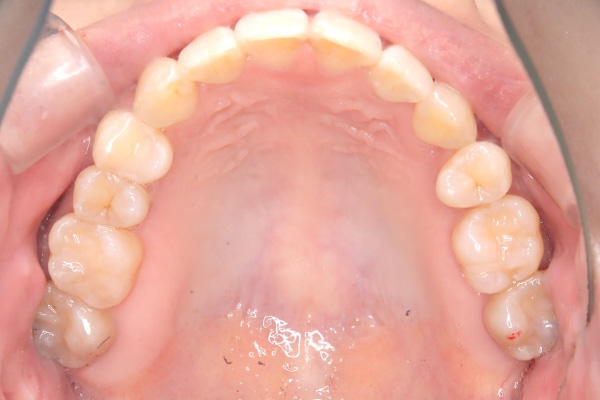

【30代女性】

八重歯と前歯で噛めないのを

インビザライン矯正で

治療したケース

治療後

| 主訴 | 八重歯、前歯で噛めないのが気になる |

|---|---|

| 期間 | 2年半 |

| 費用 | 220,000円〜660,000円 (デンタルローン 3,100〜6,600円/月) |

| 治療内容 | インザライン矯正 非抜歯 |

| 治療に伴うリスク | ・矯正終了後は、リテーナーを指示通りに使用し、歯の後戻りを防ぐ必要があります。 |